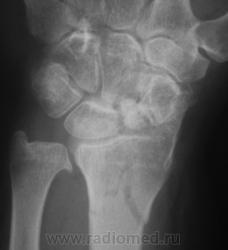

оскольчатый перелом метадиафиза лучевой кости, перелом ладьевидной кости

перелом ладьи старый в ложном суставе, выраженный, посттравматический деф.артроз л\зап сустава, ну и свежий перелом дистального метадиафиза луча, руке где то нужно сгибаться-разгибаться